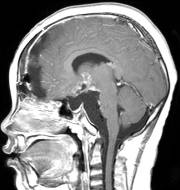

穿刺手术后患儿精神好,调养后3天行开颅手术切除肿瘤,经过14小时的艰苦奋战,顺利将肿瘤完全切除,手术后MRI见图5。患儿共住院23天,顺利康复、出院,出院时语言能力、四肢肌力均正常。

图5.手术后MRI显示肿瘤无残留迹象